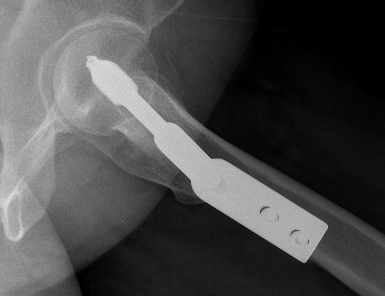

Surgery

Options

- cannulated screws

- DHS + derotation screw

- +/- minus open reduction